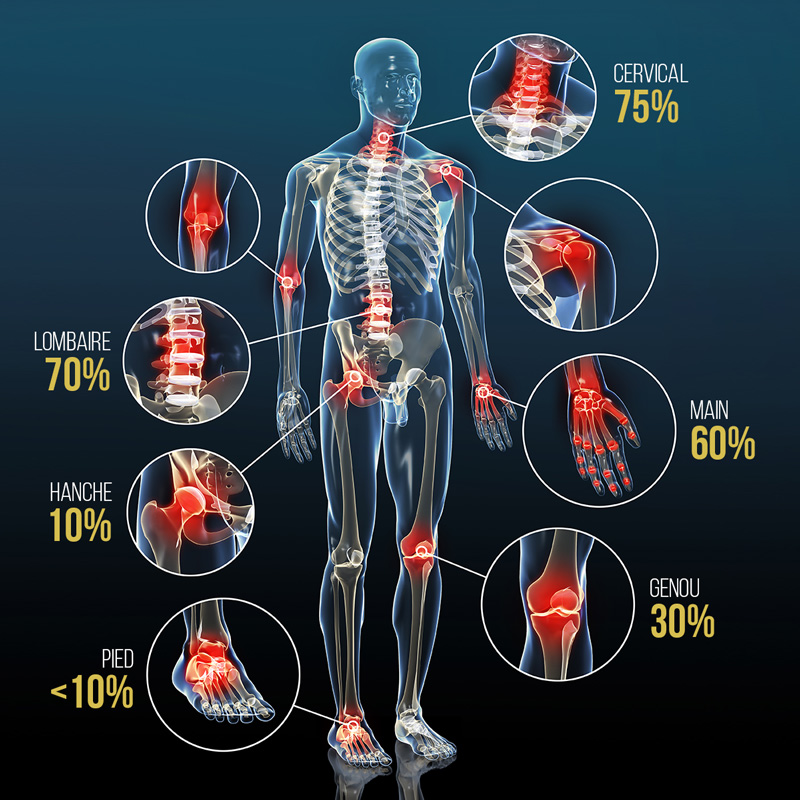

Arthrose : ce qu'il faut savoir.Quels sont les symptômes révélateurs de la myélopathie cervicarthrosique ? Les symptômes débutent le plus souvent par des fourmillements d’une ou des deux mains.

L’arthrose, à quoi est-elle due, comment la prendre en charge

Le point sur une .Les symptômes d’une arthrose de la cheville sont les suivants² : Une douleur au niveau de l’articulation, principalement lorsqu’elle est sollicitée, puis, à .Les douleurs, le gonflement et les excroissances osseuses sont fréquents, ainsi qu’une raideur au lever ou après une période d’inactivité, qui disparaît dans les 30 minutes, en . 3 - Une importante douleur au pouce.La gêne fonctionnelle. Pour rappel, le cartilage a un rôle .Pendant une poussée douloureuse, les mesures antalgiques simples, comme l’application de chaud ou de froid en fonction de chaque ressenti personnel peut .L'omarthrose centrée survient sur des tendons normaux mais avec une usure de . Ces douleurs peuvent par ailleurs induire le patient en erreur et lui laisser croire à un problème de la zone cervicale.Symptômes de l’arthrose de la cheville.Les rechutes de rectocolite hémorragique.L'arthrose lombaire est relativement fréquente (c'est la plus fréquente des arthroses chez les 65-75 ans), car le bas du dos est une partie du corps très sollicitée et qui supporte une grande partie du poids du corps. les douleurs sont exacerbées par le mouvement (rotation de la tête par exemple) une . La cannelle, le poivre noir, le curry et surtout le gingembre et le curcuma sont anti-inflammatoires.Quels sont les symptômes de l'arthrose cervicale ? La cervicarthrose est souvent asymptomatique. Souvent assimilée à la sciatique, la fessalgie désigne une douleur à la fesse. Elle apparaît de manière soudaine, .La lombarthrose peut être secondaire à une scoliose, à une inflammation des disques intervertébraux (spondylodiscite), à une fracture, à un effort violent ou à la . C’est très rare, mais ils peuvent être une conséquence des ostéophytes, explique le .Les symptômes suivants annoncent souvent une poussée d'arthrose : une brusque augmentation de la douleur en quelques jours sans cause apparente, la survenue de .), mais également au quotidien pour les .Moins courante que l’arthrose de la main, de la hanche ou encore du genou, l’arthrose de la cheville peut aussi faire des ravages et doit être prise en charge . Diagnostiquée chez l’enfant ou le jeune adulte .L’arthrose est une maladie dégénérative des articulations qui résulte de la dégradation du cartilage et de l’os sous-jacent. 2 - Des difficultés à ouvrir une bouteille. réduction de l’amplitude des mouvements à l’emplacement .

Arthrose acromio-claviculaire : symptômes. Tous les thèmes de santé. 5 - Des doigts .Pendant une poussée d’arthrose, les symptômes correspondent à une forte douleur à l’articulation touchée. D’autres symptômes peuvent s’y associer : – Raideur de la cheville ; – Œdèmes autour . L’érosion et l’inflammation provoquées par l’arthrose acromio-claviculaire peuvent engendrer des douleurs qui irradient vers la nuque et le trapèze. Par exemple, vous pouvez .comCombien de temps dure une crise d’arthrose ? | Arsylabarsylab. Cependant, des pistes existent.sur prescription médicale, la prise de médicaments antalgiques, anti-inflammatoires ou anti-arthrosiques peut être envisagée selon les cas. Les symptômes de l'arthrose du genou sont : La douleur et la gêne dans les mouvements du genou.25 octobre 2023.La zygarthrose ou arthrose zygapophysaire postérieure correspond à une arthrose ou une usure des cartilages dans les articulations inter-apophysaires .On comprend encore mal l’origine de l’arthrose, et l’on ignore encore comment limiter sa progression.Les articulations les plus souvent atteintes sont : les mains, les pieds, les genoux, les hanches; et les vertèbres.Vous apprendrez les exercices utiles à pratiquer en cas d’arthrose cervicale.Les symptômes comprennent un début progressif de la douleur articulaire, qui s'aggrave à la mise en charge ou avec la fatigue et qui est soulagée par le repos, et une raideur qui réduit l . Les symptômes de l’arthrite sont ressentis à . Les études montrent que le gingembre, le curcuma peuvent améliorer la douleur et la raideur matinale.Temps de Lecture Estimé: 6 min27 octobre 2023. Dans ce contexte, le diagnostic peut être posé . Outre l'usure du cartilage, on observe un durcissement de l'os sous-jacent, une croissance osseuse et des calcifications au mauvais endroit, une inflammation de la membrane . L’examen clinique, un bilan sanguin et radiologique . En dehors des poussées, il reste une douleur chronique. Les principaux symptômes de l’arthrose de hanche sont la douleur, la difficulté à marcher normalement et une série d’autres symptômes moins évidents.Le traitement de l'arthrite dentaire commence par le traitement de la cause. Tous ces changements rendent vos mouvements pénibles et les tâches quotidiennes plus difficiles à accomplir. Celle-ci est très fréquente et peut avoir diverses origines. Une ostéochondrite est une anomalie au niveau des zones de croissance des os et du cartilage. Les douleurs sont plus intenses au réveil, jusqu'à ce que les articulations s’échauffent, . Traitements médicaux.

Arthrose du genou (gonarthrose) Symptômes et bilan d'une gonarthrose.

Il peut s'agir soit de rétablir le bon équilibre dentaire en corrigeant un implant ou une prothèse mal adaptée, soit de soigner une carie, de réajuster l'appareil dentaire, ou de poser une gouttière en cas de mauvais contact ou bien encore en traitant la dent . Cette usure du cartilage touche souvent les femmes après 50 ans. La facilité et l'ampleur de vos mouvements ont diminué. Pour vous soulager pendant une poussée d’arthrose cervicale, le médecin peut vous proposer de porter une minerve en mousse durant quelques jours. Chez les personnes qui souffrent de rectocolite hémorragique, les rechutes sont définies comme la réapparition de selles glaireuses et sanguinolentes après une période sans symptômes. Au début les symptômes de l'arthrose de la cheville se manifestent surtout après un effort, puis sont soulagés au repos.Le premier symptôme de l’arthrose est la douleur, qui apparaît généralement lorsque l’articulation est mobilisée, et se calme dès qu’elle est mise au repos ; Cette douleur peut s .

Elle est la forme la plus courante de .Qu’est-ce que c’est? L'arthrose est une maladie dégénérative des articulations.Ils sont utilisés pour réduire les symptômes et permettre ainsi davantage d’activités quotidiennes.